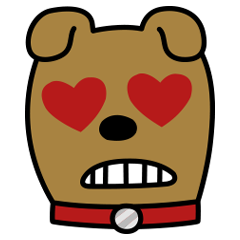

소흉근/작은가슴근 Pectoralis Minor

기시점

갈비연골 제 3-5

정지점

어깨뼈부리돌기

작용

어깨뼈의 내밈, 내림 그리고 아래돌림

신경지배

안쪽가슴신경(C8,T1)

Origin

rib 3-5

Insertion

coracoid process

Action

protraction, depression, downward rotation of scapula

Innervation

medial pectoral nerve(C8,T1)